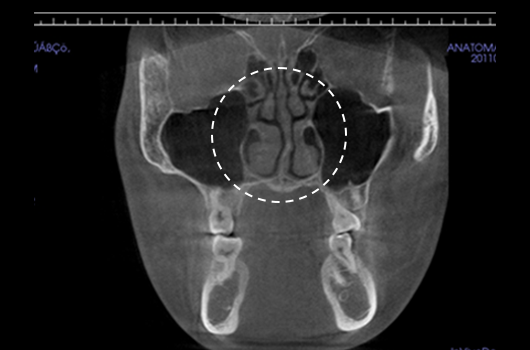

Operasi hidung CT 3D membantu pelaksanaan operasi hidung yang lebih canggih setelah menganalisis wajah secara cermat untuk menentukan mana yang terbaik.Analisis tiga dimensi digunakan untuk mengetahui keadaan secara umum, ukuran, bentuk, dan asimetri tulang hidung, tulang rawan septum hidung, dan jaringan kulit, yang tidak dapat ditentukan melalui konsultasi pada umumnya. Saat merencanakan revisi operasi hidung, kami dapat memeriksa elemen fungsional seperti deviasi septum hidung, bentuk implan yang ada, termasuk implan silikon, atau komplikasi dari operasi sebelumnya.

Pentingnya 3D-CT Scan pada Operasi Hidung

Dalam setiap konsultasi operasi hidung, Klinik Operasi Plastik Braun menggunakan 3D-CT scan untuk menganalisis isu-isu berikut dalam tiga dimensi: Rancangan bedah dapat dibuat lebih tepat dan potensi efek samping dapat berkurang dengan memahami lebih lanjut ukuran, bentuk, dan asimetri bagian hidung yang tak kasat mata dan struktur anatomi disekitarnya sebelum operasi.

1. Analisis tulang rawan septum dalam berbagai ukuran dan bentuk

2. Diagnosis dan tindakan untuk deviasi hidung dan deviasi septal

3. Analisis untuk lebar dan asimetri tulang hidung

4. Diagnosis Inferior turbinate asymametry dan pembedahan hidung tersumbat